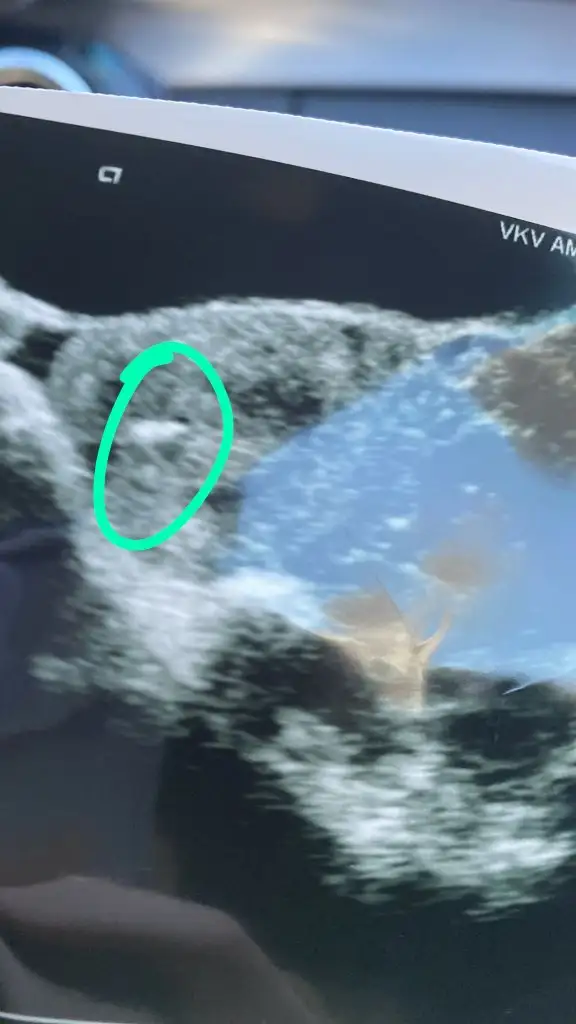

bak bunlarKızlar size embriyonuzun ultrason şeklinde fotoğrafını verdiler mi

Sana transferden sonra verilmiş bana transferden önce verildi embriyonun fotosubak bunlar

aaa ilk defa bunu görüyorum anaamm yavyumm deseydin:)) çok acayip şeyler bunlar yaaozmut Buda benimki transferde sonra istemeyi unuttum çift embriyo şokuyla

Ah o duygu ışık gibi parlıyordularbana aldı bak burda diyor hemşire dedim hani nerde göremiyorum